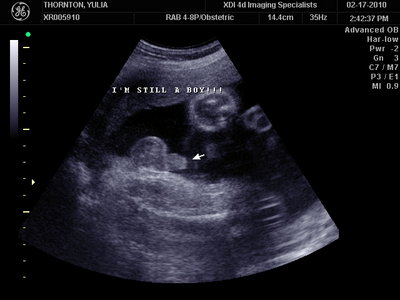

А это в 30 недель

| Вложения: |

MY BABY SONO!_20.JPG [ 94.63 КБ | Просмотров: 1034 ]

Sweetheart75 писал(а): Ну ладно, тогда и я нашего писюна покажу  Надеюсь, Джеффри на меня не обидится Вот это в 23 недели: (там оборудование переключалось из режима 3Д в обычный 2Д) Oоо, такое достоинство невозможно не заметить  А в 30 недель так вообще!